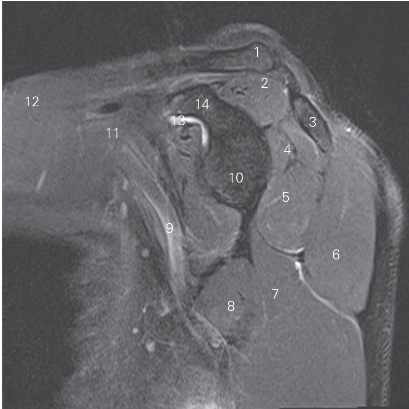

图4-22 经肩关节盂的矢状断层MR T2WI FS

1 锁骨 clavicle 2 冈上肌 supraspinatus

3 肩胛冈 spine of scapula 4 冈下肌 infraspinatus

5 小圆肌 teres minor 6 三角肌 deltoid

7 肱三头肌长头 long head of triceps brachii

8 大圆肌 teres major

9 腋窝血管神经束 axillary neurovascular bundle

10 关节盂 glenoid cavity 11 胸小肌 pectoralis minor

12 胸大肌 pectoralis major

13 喙突下滑囊 bursa mucosa of inferior coracoid pocess

14 喙突 coracoid prcess